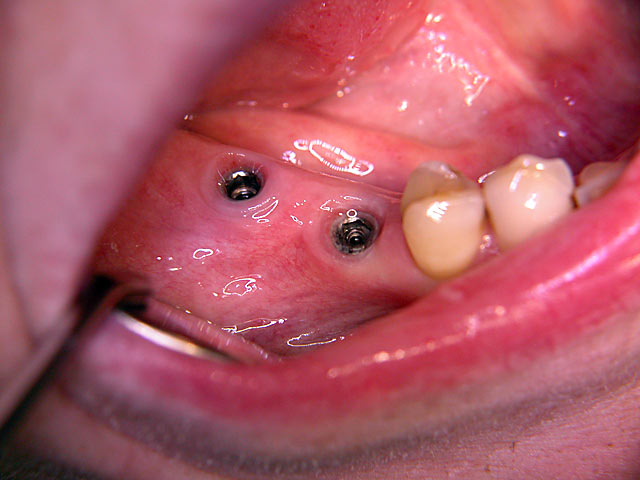

Sofort-Implantation: